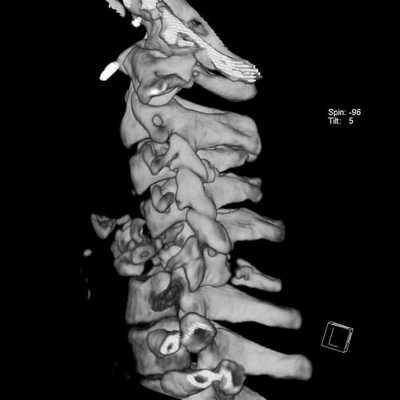

4. КТ костного трансплантата позвоночника:

• Бесконтрастная КТ:

о МСКТ позволяет оценить положение трансплантата, целостность замыкательных пластинок, диагностировать перелом трансплантата, тел позвонков

4. КТ при несостоятельности металлоконструкции позвоночника:

• Костная КТ:

о Периимплантные просветления (позволяют заподозрить расшатывание импланта)

о Распространение винта за пределы задней покровной пластинки позвонка при бикортикальном введении винтов на уровне шейного отдела позвоночника

о Пенетрация медиальной стенки корня дуги при субоптимальном введении педикулярных винтов